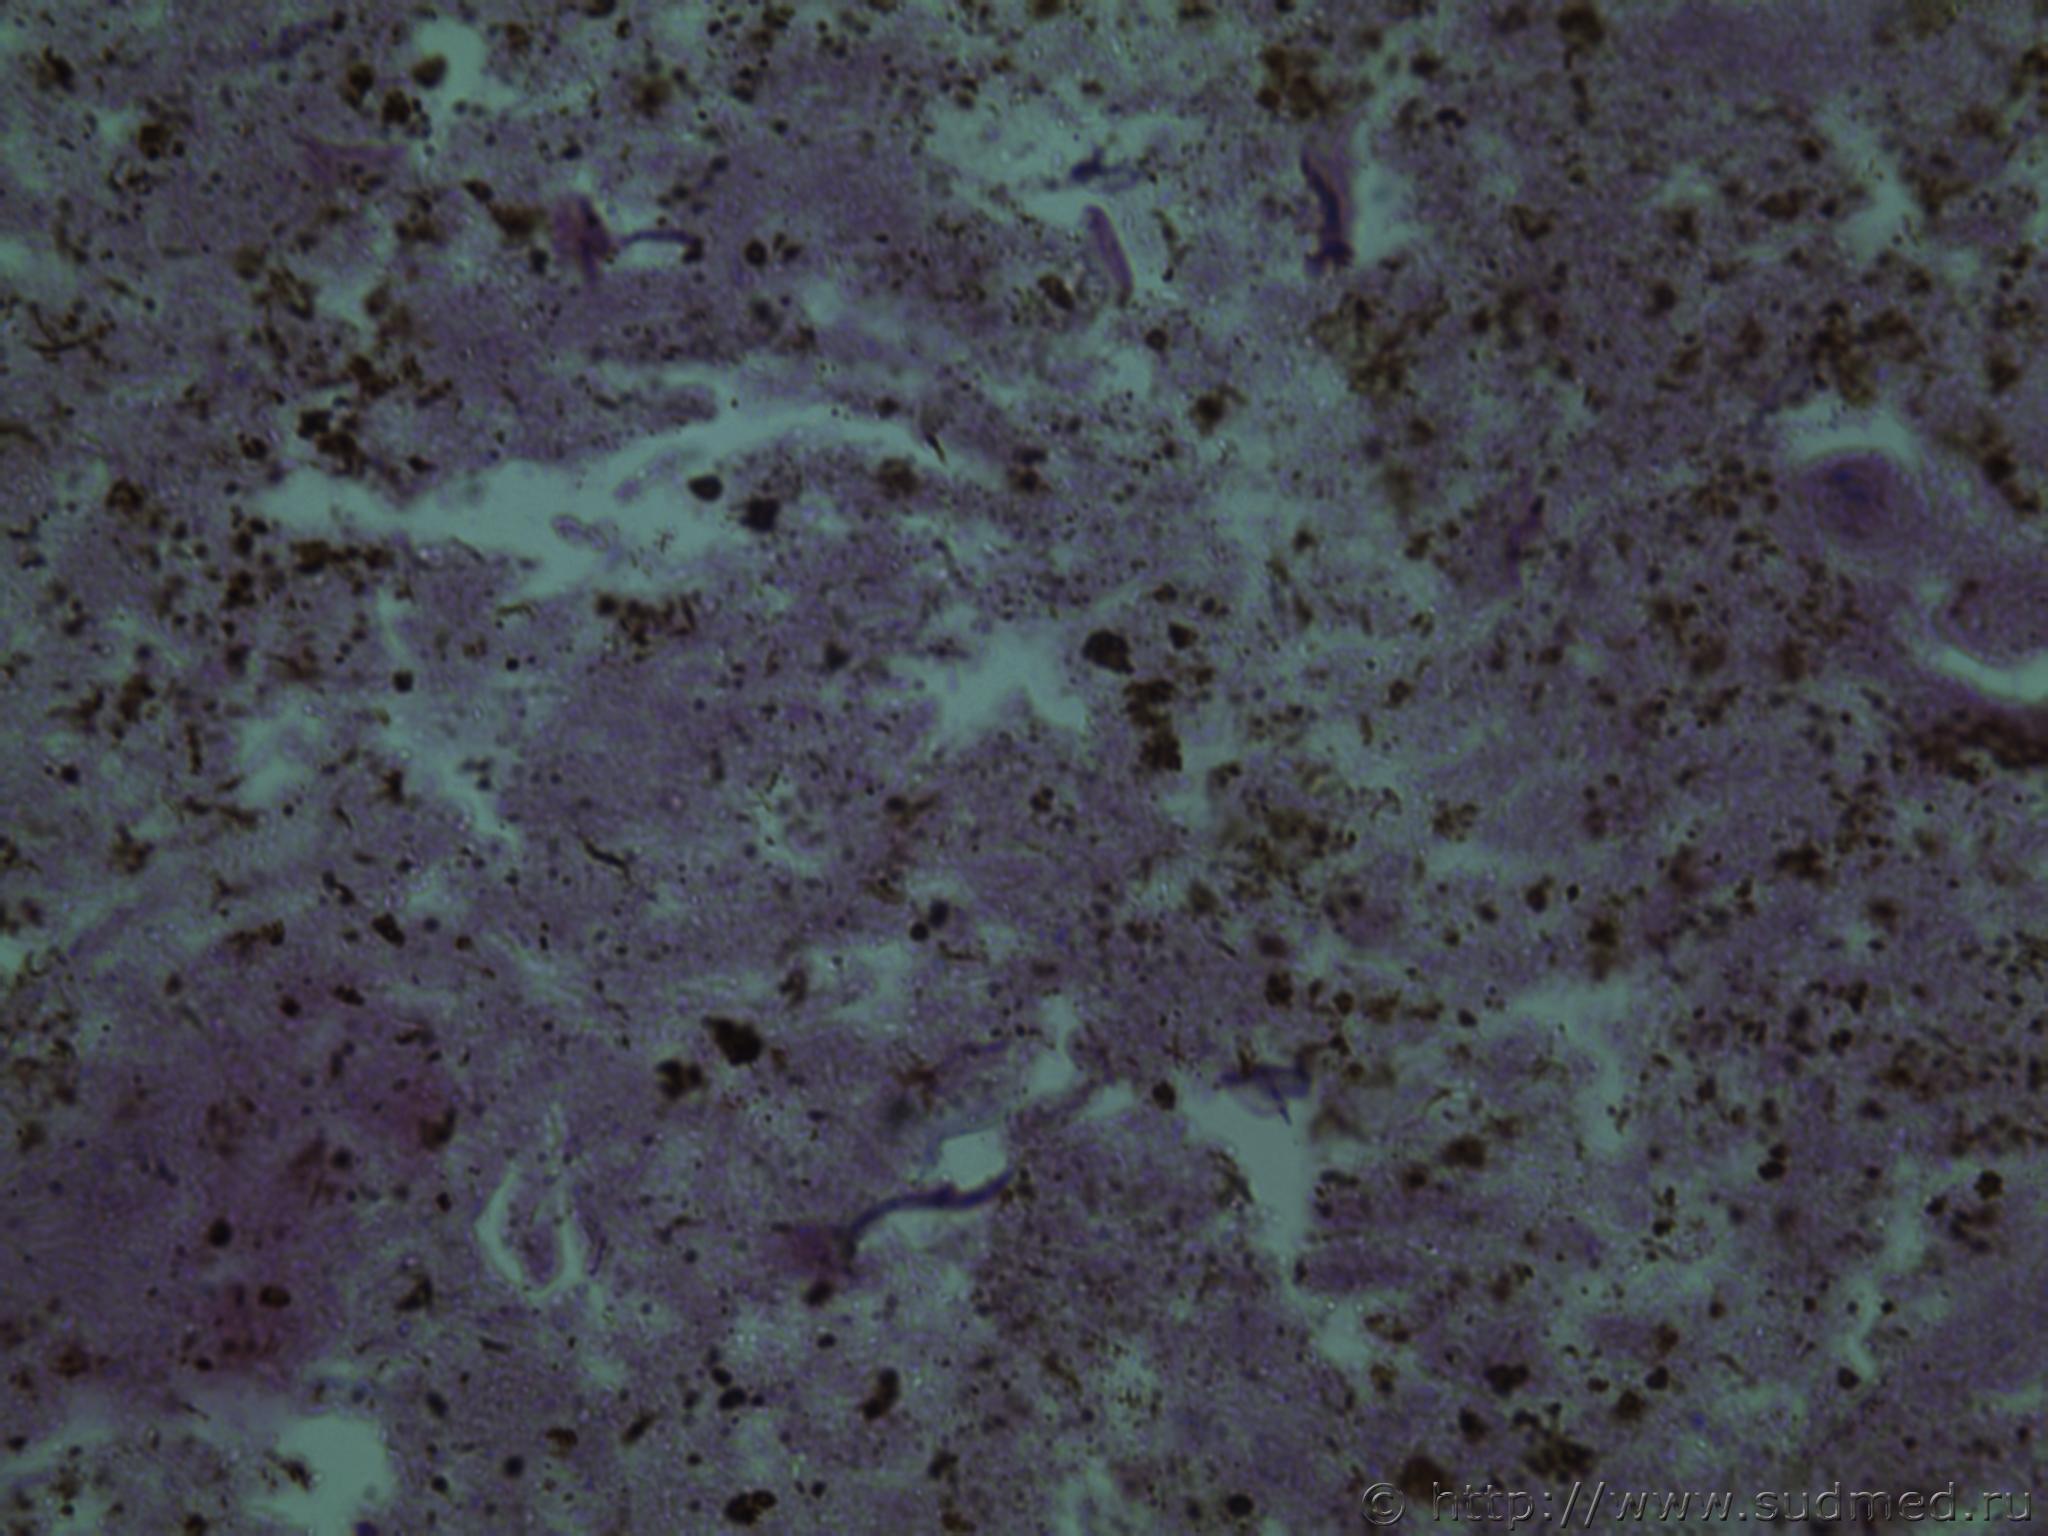

всем здравствуйте. хотела бы знать ваши мнения. провожу экспертизу. препараты как и труп новорожденного гнилые либо в аутолизе страшном. в легком картина такова, что ткань "плотная". просвет различимых альвеол в виде щелей и по всем полям зрения элементы околоплодных вод. одна артерия пуповины спазмирована. остальные сосуды непонятно : просвет их спавшийся но без признаков спазма. они как будто сплющены. да и сама пуповина в виде тонкого тяжа, видно из-за гнилостных изменений. под тмо спинного мозга признаки кровоизлияния, как и в коже с шеи. в коже головы с полнокровием отдельных сосудов. мать утверждает что ребенок после родов не сразу но все же шевелился и кричал. хотя перед этим он выпал у нее из матки на пол, ударившись головой. и со слов матери у него была пена изо рта и он хрипел.

сегодня сфоткаю конечно. но не факт что будут качественные фотки. плавательная проба - "сомнительная".

Судебная медицина - Прикрепленное изображение Судебная медицина - Прикрепленное изображениеСудебная медицина - Прикрепленное изображениеСудебная медицина - Прикрепленное изображениеСудебная медицина - Прикрепленное изображение

Плохо,материал гнилой.

Остановился бы на дышавшем лёгком.

В данном случае лучше вообще уйти от ответа и ограничиться фразой "в виду аутолиза и признаков универсального гниения в ткани лёгкого судить о прижизненном наличии воздуха в альвеолах не представляется возможным"

5 фото в сообщении №4 и 8 фото в сообщении №5 не наводит ли на мысль о дышавшем лёгком ?

Про остальные фото молчу,там или ничего не видно или же есть оптически пустые пузыри,что вероятнее всего,проявления гниения.